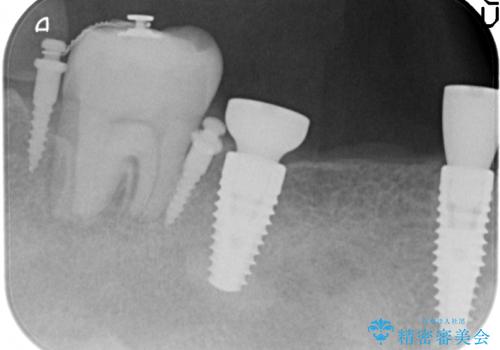

長いブリッジをインプラント補綴への変更

- 右下に入れた長いブリッジが噛むといたみ、改善を希望され来院されました。

長いブリッジは支台となる歯の過大な負担となることが多く、歯の破折や揺れ・痛みの原因となり得ます。

支台を増やし、残った歯の負担を減らし守るために欠損部位にインプラントを埋入し咬合力の負担に対応できる環境を整えます。

- 105.4万円(仮歯×4・ストローマンインプラント×2・チタンカスタムアバットメント×2・ジルコニアクラウン×4)費用は治療当時の料金となります

インプラント治療は、ブリッジや入れ歯と異なり人口の歯根となるインプラントを顎骨内に埋入することで咬合力に耐える支台を増やせるというメリットがあります。

残った歯の負担を減らすことでより長期的な予後を期待することができます。